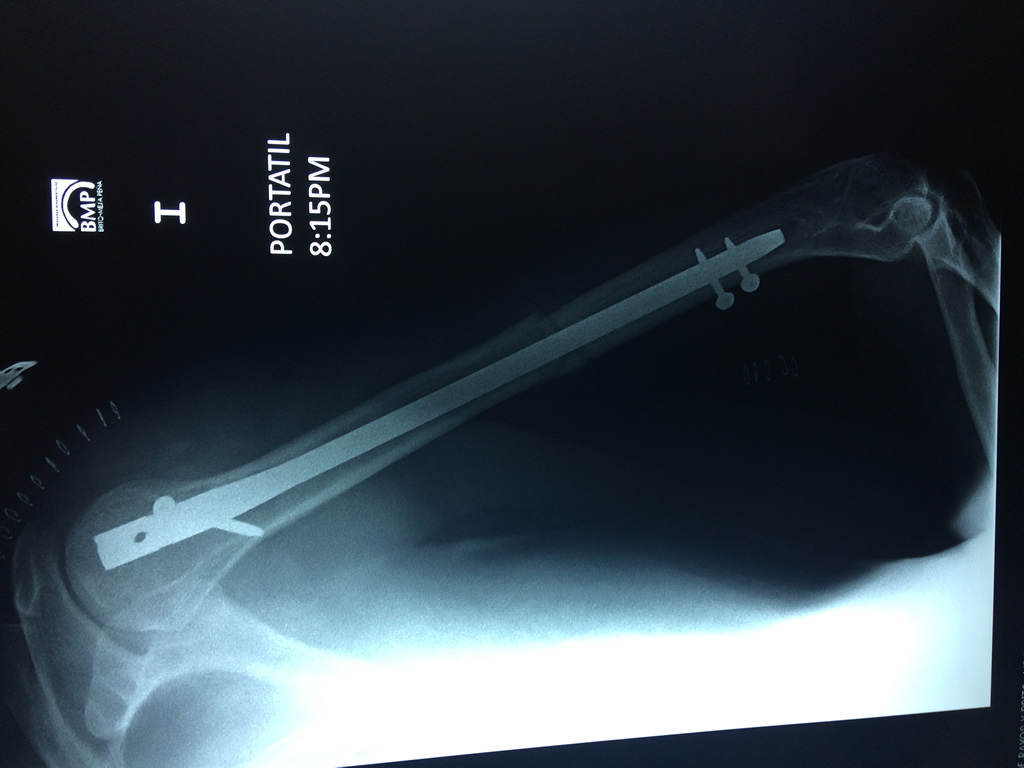

Cirugías de Codo - Húmero

El Húmero (en latín, humerus) es el hueso más largo de las extremidades superiores en el ser humano. Forma parte del esqueleto apendicular superior y está ubicado en la región del brazo. ... El extremo proximal del húmero tiene la cabeza, cuellos quirúrgico y anatómico y tubérculos mayor y menor.